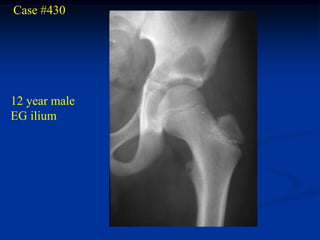

Case #430

12 year male

EG ilium